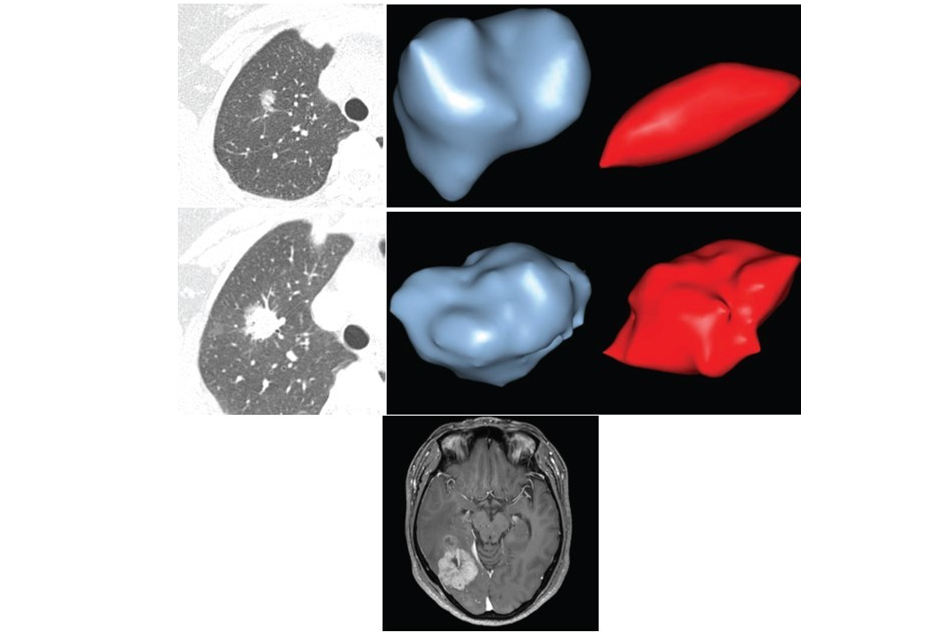

The talk focused on the 61 cancers found in a subset of patients (24 male and 37 female; age range 53-79 years; mean age, 65 years), and particularly on the 48 cancers that were imaged more than once in annual CT screening, which offered an opportunity to measure the doubling time of solitary pulmonary nodules that were eventually diagnosed as lung cancer.

The retrospective study sought to evaluate the size, morphology, location, and morphologic change of lung nodules, and the growth rate of both incidence and prevalence of lung cancers detected in high-risk participants who underwent annual screening chest CT scans over a five-year period. The researchers also evaluated lung cancer histology and staging.

Attenuation changes occurred in 44% (21/48) of the tumors imaged more than once, the researchers reported in their abstract. Margin changes occurred in 42% (20/48), most often more irregular or spiculated (16/20, 80%).